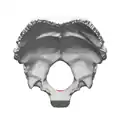

![]() Occipital bone. Inner surface. | |